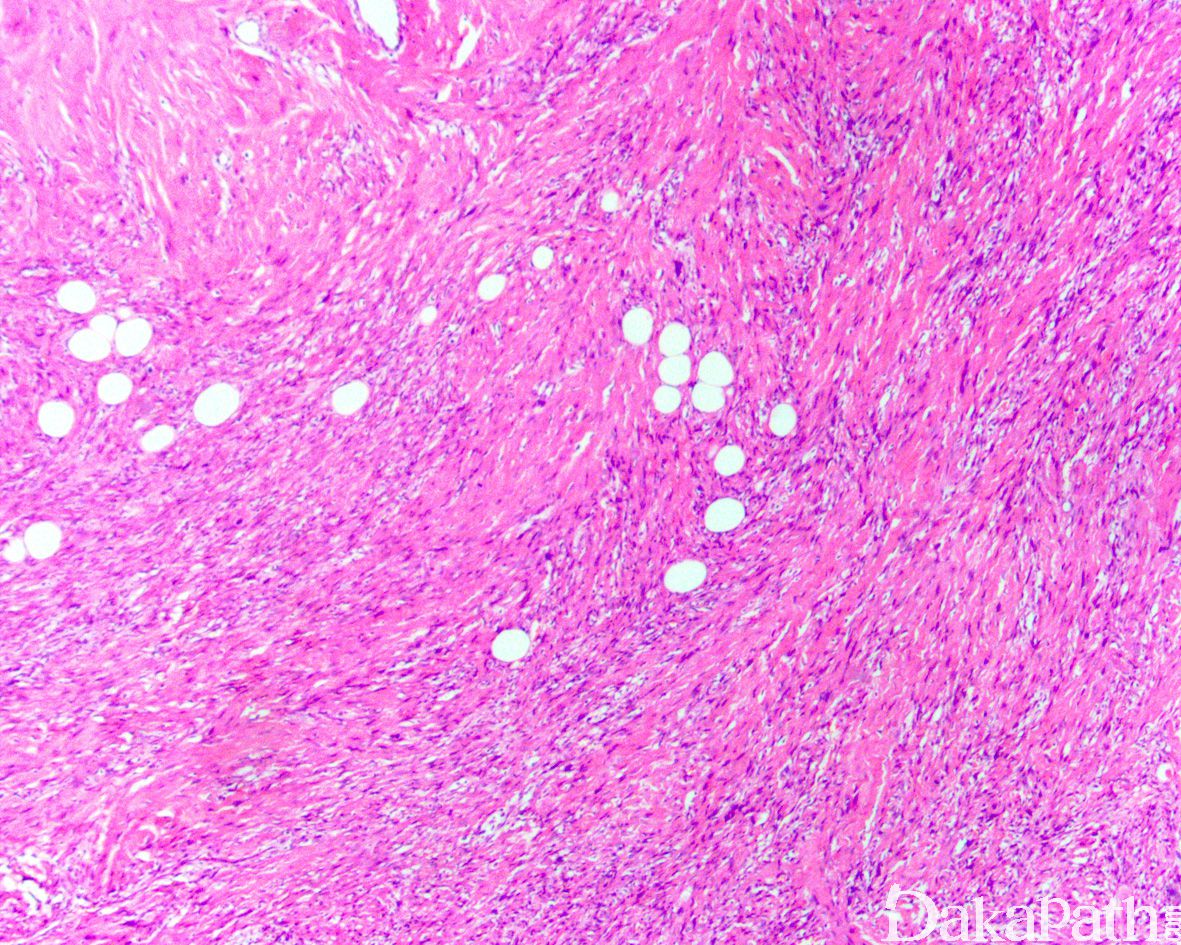

镜下见由长梭形细胞呈束状排列,也可呈席纹状、交织的束状或漩涡状排列,或呈波浪状排列;

少数病例可见典型的原始胚胎性横纹肌肉瘤成分;

间质可见数量不等的胶原纤维。